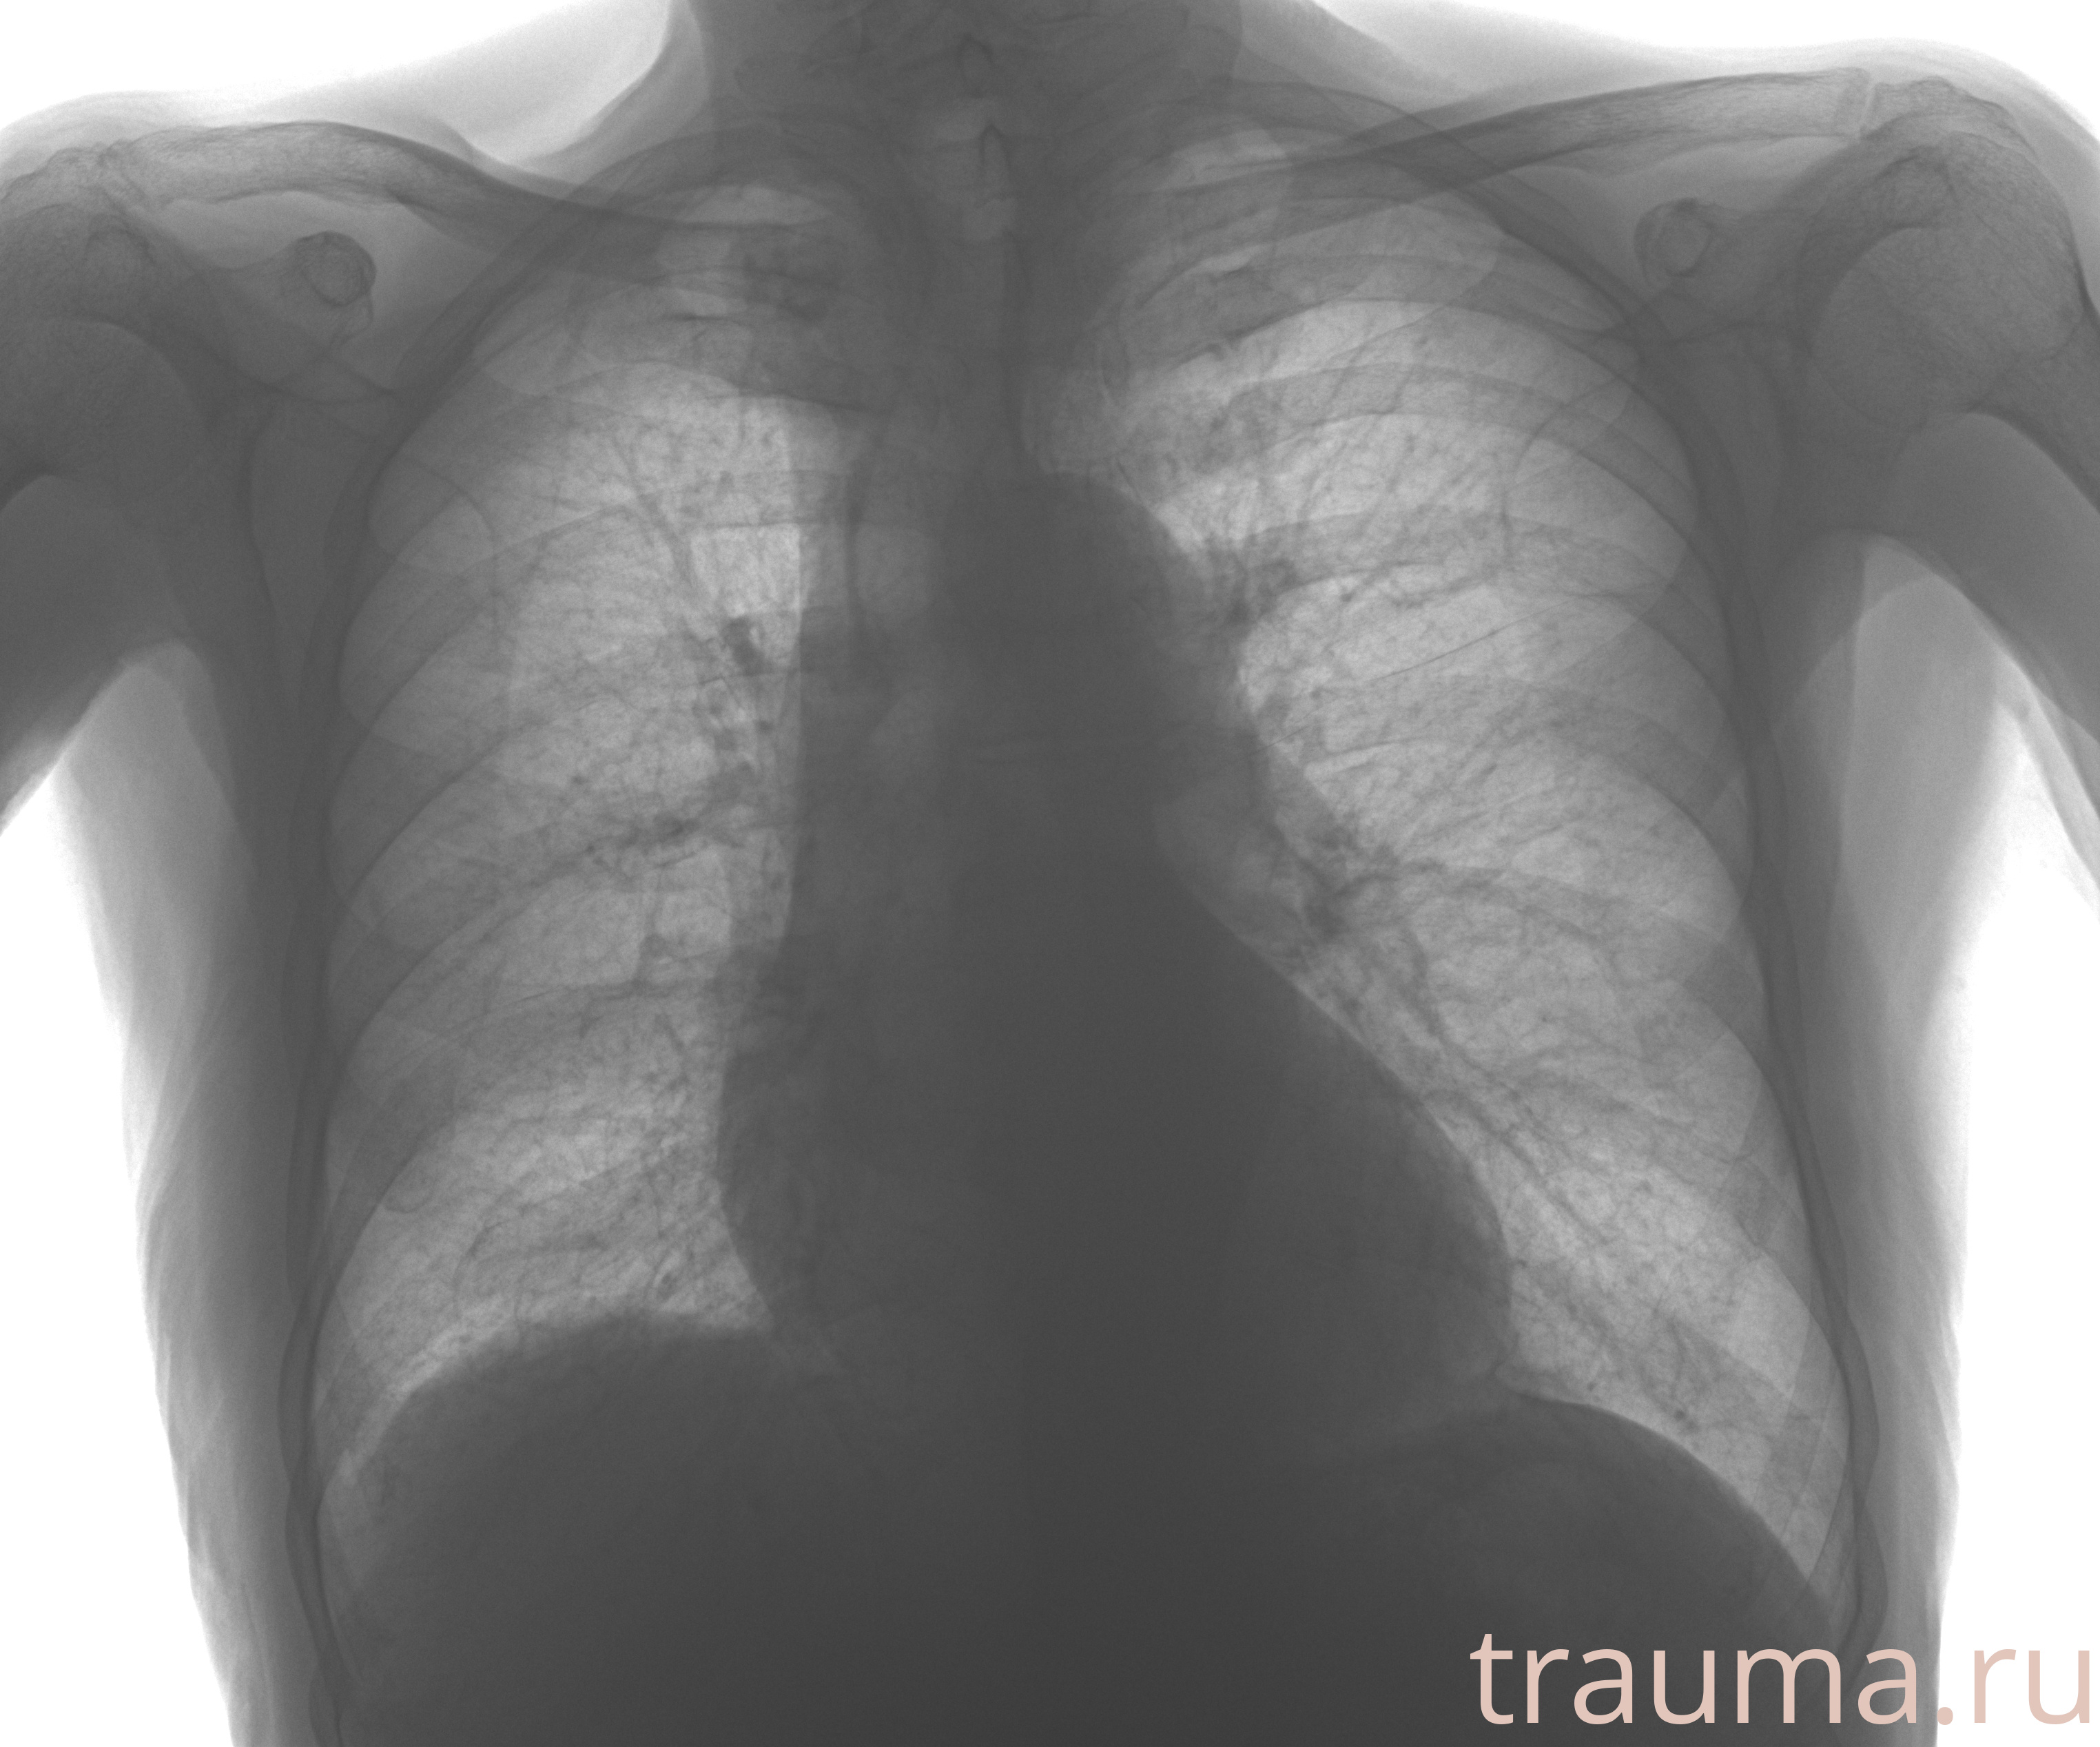

Рентгенограммы

Рентген на дому: по вашему адресу приезжает врач-рентгенолог, травматолог-ортопед с мобильным рентгеновским аппаратом, проводит диагностику травмы или заболевания, делает необходимые рентгенограммы, дает рекомендации по дальнейшему лечению. Получить качественные снимки в домашних условиях возможно благодаря уникальной методике, разработанной МосРентген Центром для института  Склифосовского